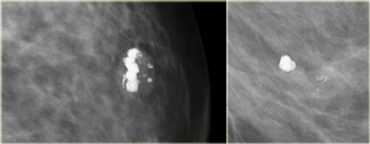

LEFT: cluster of pleiomorphic calcifications on oblique viewRIGHT: milk of calcium (teacups) on lateral view with horizontal beam LEFT: cluster of pleiomorphic calcifications on oblique viewRIGHT: milk of calcium (teacups) on lateral view with horizontal beam

Many calcifications representing milk of calcium within microcysts however do not layer on horizontal beam radiographs.

The most important feature of these calcifications is the apparent change in shape of the calcific particles on different mammographic projections (craniocaudal versus oblique or 90? lateral).

The images show a different shape on the oblique view compared to the mediolateral view.

On the mediolateral view there is layering of the calcium.

Milk of calcium Milk of calcium

On the craniocaudal image the calcifications are round, fuzzy and ill-defined.

On the mediolateral view the calcifications appear as semilunar, crescent shaped tea cups.

Click on the image for an enlarged view.